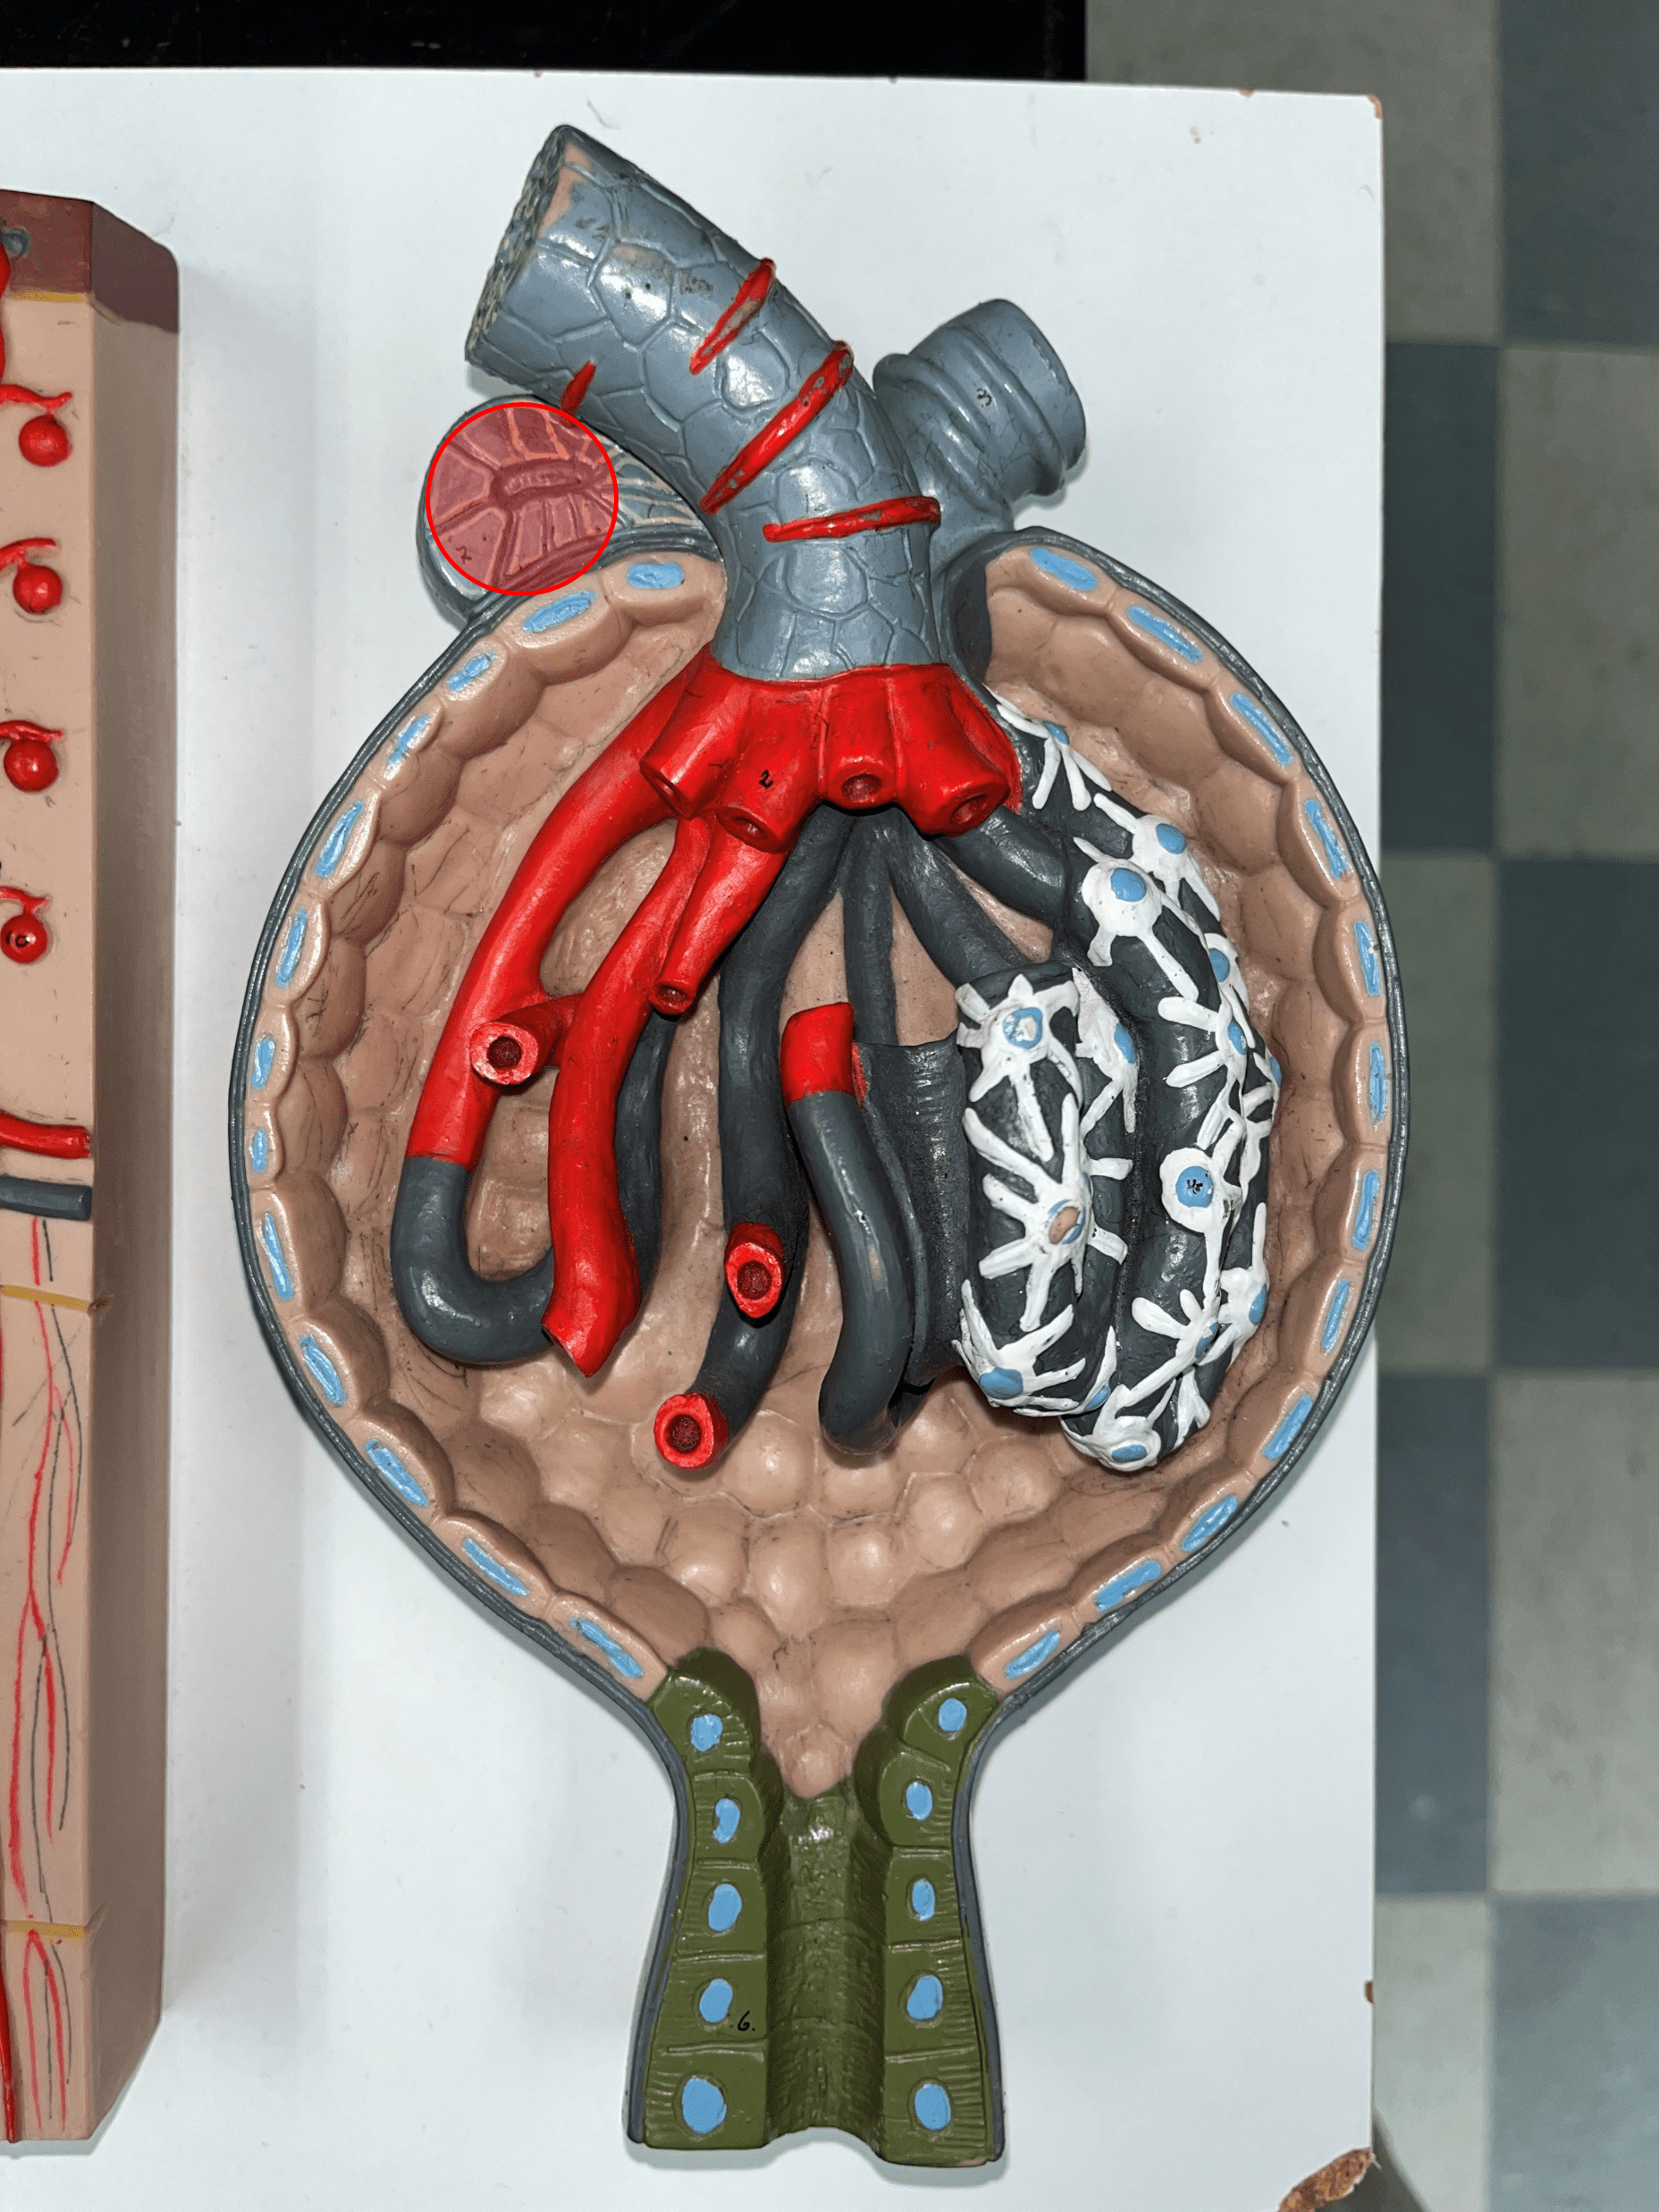

renal pyramid

• A triangular structure found in the renal medulla.

• The base faces the renal cortex.

• The renal papilla (apex) faces the renal pelvis.

• The base faces the renal cortex.

• The renal papilla (apex) faces the renal pelvis.

renal papilla

The apex of the renal pyramid facing the renal pelvis.

renal cortex

• The outermost region of the internal kidney.

• Superficial to the renal medulla.

• Appears slightly granular.

• Superficial to the renal medulla.

• Appears slightly granular.